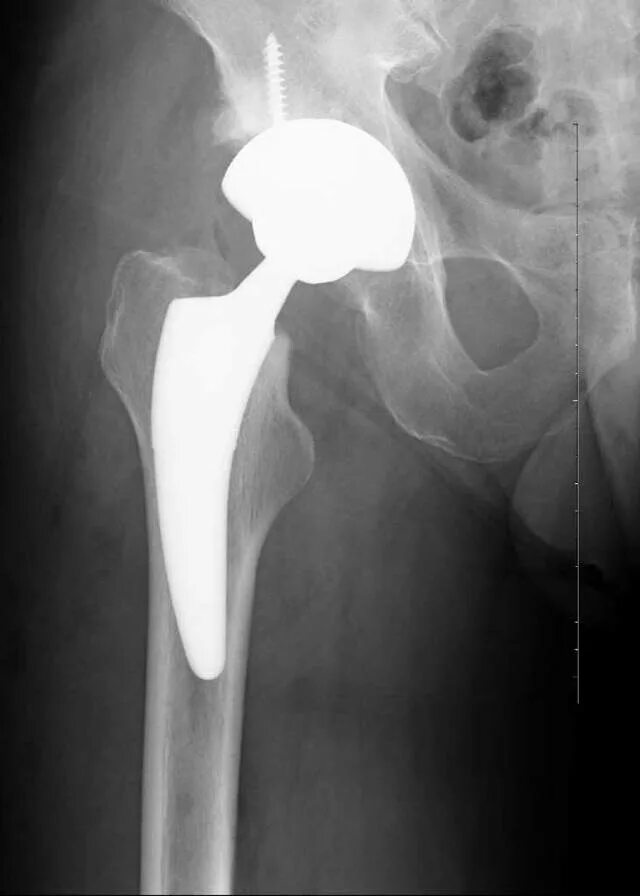

Можно ли эндопротезом делать мрт